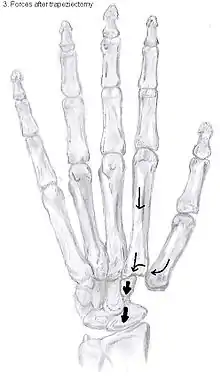

Trapeziectomy

During trapeziectomy,[30] the trapezium bone is removed without any further surgical adjustments.The trapezium bone is removed through an approximately three centimeter long incision along the lateral side of the thumb. To preserve surrounding structures, the trapezium bone is removed "by splitting" it into pieces.

An empty gap is left by the trapeziectomy and the wound is closed with sutures. Despite this gap, no significant changes in function of the thumb are reported.[27] After the surgery, the thumb will be immobilized with a cast.